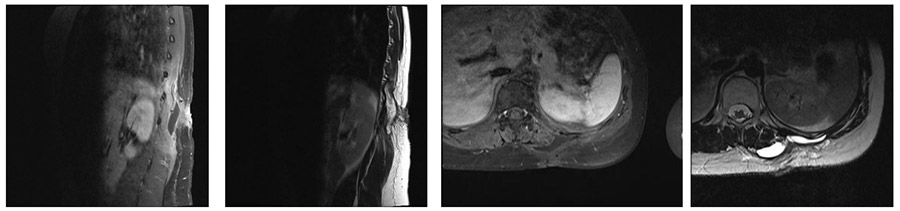

Ameliyat Öncesi: MR’da operasyon alanında kalıntı tümör dokusu ve sıvı birikimi görülmekte